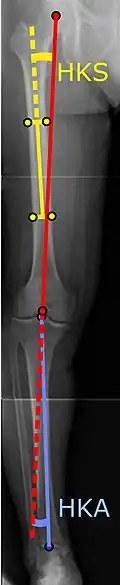

![]() |

Angles commonly measured before knee replacement surgery: |

To indicate knee replacement in case of osteoarthritis, its radiographic classification and severity of symptoms both should be substantial. Such radiography should consist of weightbearing X-rays of both knees: AP, lateral, and 30 degrees of flexion. AP and lateral views may not show joint space narrowing, but the 30-degree flexion view is most sensitive for narrowing. Full-length projections also are used in order to adjust the prosthesis to provide a neutral angle for the distal lower extremity. Two angles used for this purpose are:

- Hip-knee-shaft angle (HKS),[14] an angle formed between a line through the longitudinal axis of the femoral shaft and its mechanical axis, which is a line from the center of the femoral head to the intercondylar notch of the distal femur.[16]

- Hip-knee-ankle angle (HKA),[15] which is an angle between the femoral mechanical axis and the center of the ankle joint.[16] It is normally between 1.0° and 1.5° of varus in adults.[17]